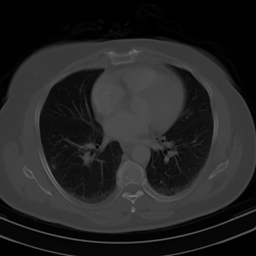

This result implies that random noise can also produce undesirable effects. In Fig. 3 we show several examples of this effect. For the first DL method, mean zero Gaussian noise causes the NN reconstruction map to hallucinate, by artificially removing an image feature (indicated by the red arrow). In the second case, certain image independent, small mean Gaussian noise causes severe instabilities in the recovered image. Notice that the noise causes the second DL method to exhibit completely nonphysical artefacts, which could be easily identified by a practitioner as a failure mode. Yet for the first method it creates seemingly realistic artefacts (hallucinations). Such pernicious artefacts may be impossible to detect.

Hallucinations with zero-mean Gaussian noise Instabilities w.r.t. to Gaussian noise with image independent mean

Noisy image: Noisy image:

|x+v|𝑥𝑣|x+v| |x+v|𝑥𝑣|x+v|

(full size) (cropped)

Refer to caption Refer to caption

DeepMRI-net: DeepMRI-net:

|Ψ(A(x+v))|Ψ𝐴𝑥𝑣|\Psi(A(x+v))| |Ψ(Ax)|Ψ𝐴𝑥|\Psi(Ax)|

(cropped) (cropped)

\begin{overpic}[width=433.62pt]{plots/im_noise1_fact_3_rec_worst_100_place_2_crop.png} \put(68.0,42.0){\color[rgb]{1,0,0}\definecolor[named]{pgfstrokecolor}{rgb}{1,0,0}\vector(1,4){6.0}} \end{overpic} Refer to caption

AUTOMAP: AUTOMAP:

Ψ(Ax+e0)Ψ𝐴𝑥subscript𝑒0\Psi(Ax+e_{0}) Ψ(Ax+e1)Ψ𝐴𝑥subscript𝑒1\Psi(Ax+e_{1})

(full size) (full size)

Ψ(Ax+e2)Ψ𝐴𝑥subscript𝑒2\Psi(Ax+e_{2}) Ψ(Ax+e3)Ψ𝐴𝑥subscript𝑒3\Psi(Ax+e_{3})

Figure 3: (Hallucinations and instabilities due to random noise) Two DL methods exhibit hallucinations and instabilities due to random noise. On the left, the DeepMRI-net [66] reconstruction map is unstable to mean-zero Gaussian noise v𝑣v. In this case, the NN hallucinates by removing a key image feature (see the red arrow). On the right, the AUTOMAP [82] reconstruction map is unstable to Gaussian noise. The noise vector e0subscript𝑒0e_{0} is drawn from a zero-mean Gaussian distribution, whereas the mean of the distribution, used to generate e1,e2subscript𝑒1subscript𝑒2e_{1},e_{2} and e3subscript𝑒3e_{3}, is based on three worst-case noise vectors computed for AUTOMAP with respect to a different image. This makes the mean is image independent. As we can see, the instability of the map produces noticeable artefacts. The measurement matrix in these experiments is a subsampled Fourier transform with 33% (left) and 60% (right) subsampling, respectively. See §A for further information.